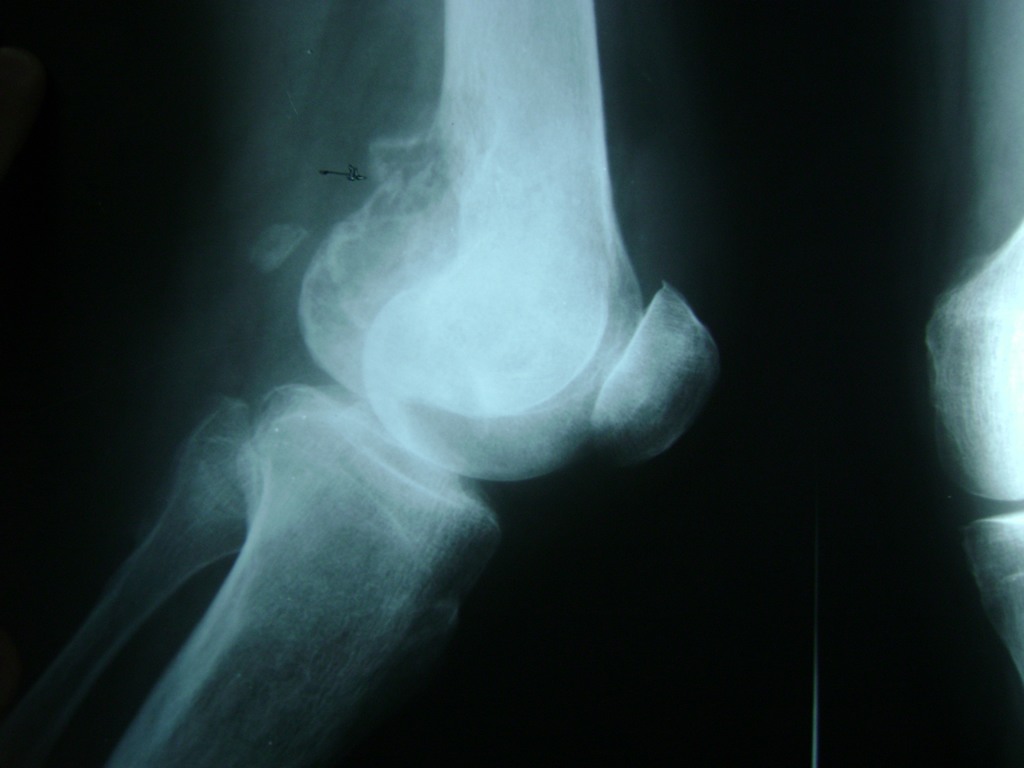

La artroscopia de rodilla es un cirugía en el cual la estructura interna de la articulación es examinada ya sea para realizar un diagnostico o para realizar un tratamiento, este procedimiento se realiza utilizando un instrumento parecido a un pequeño tubo llamado artroscopio.